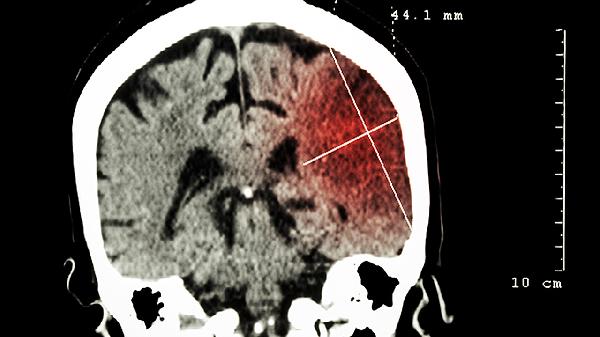

久强脑立清可增加脑部血流量,缓解椎基底动脉供血不足导致的视物旋转、站立不稳等症状。耳鸣耳聋等内耳微循环障碍症状也可能得到减轻。